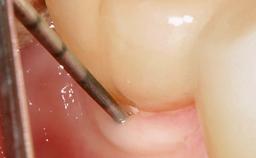

Late Presentation of Peri-Implant Mucositis Requiring Soft-Tissue Augmentation and Esthetic Crown Lengthening at Implant Site 11

Biological or technical complications around implant-supported prostheses place a significant burden on patients as well as the surgical and restorative team. Inflammation of the peri-implant soft tissues is often the first sign that something has gone awry. While there is never a good time for a complication, late presentation of inflammation in the soft tissues around a long-standing prosthesis triggers a period of research and review of the case in order to ascertain the treatment history and its possible contribution to the etiology of the situation. This becomes more complicated in situations where a patient has not received regular maintenance and clinical/radiographical examinations due to personal, financial, or professional reasons. When the complication occurs in the esthetic zone, the complexity of the situation expands exponentially, as the only acceptable outcome in the patient’s eyes will be the maintenance of the esthetics of the prosthesis.